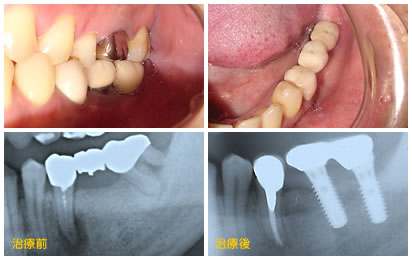

治療前

インプラント治療前左側下顎7番エクトリュージョンさせて、骨を新生させた上でインプラント植立した症例

初診時下顎口腔内写真と同左側側方面観

治療後

治療後のインプラント

インプラント治療後口腔内写真(左上)

同咬合面観(右上)

下の2枚の写真は、治療前後のパノラマレントゲン